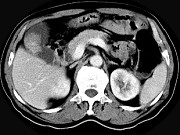

- 单项选择题男,45岁, 右季肋区疼痛,Murphy征阳性, B超提示胆囊息肉,CT所见如图, 最可能的诊断为 ( )